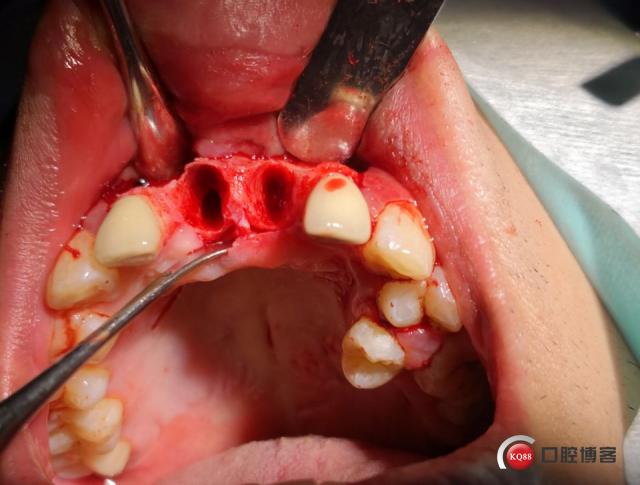

种植体周围炎:

(图片来源网络,侵删)- 症状:牙龈红肿、出血、溢脓、种植体松动、牙龈萎缩。

- 原因:口腔卫生不佳、咬合力过大、吸烟等导致细菌感染,破坏骨结合。

- 处理:需立即进行专业治疗(清创、抗菌药物、骨增量等),否则可能导致种植体脱落。